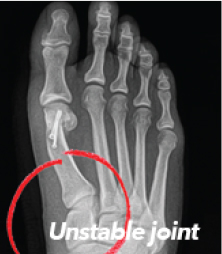

Bunions can be very painful. With each step, your entire body weight rests on that bunion. Ouch! A common misconception about a bunion is that it is an overgrowth of bone that can simply be "shaved off". In reality, bunions are complex deformities caused by an unstable joint.

For 87% of people with bunions, traditional surgery has failed to get to the true source of the problem – a 3-dimensional deformity caused by an unstable joint.2 This is why many people who have had traditional surgery have had their bunions return.3 In fact, 1 in 3 patients have been left dissatisfied with their surgical outcome in the past and up to 70% of those treated have had their bunion return.4

Traditional bunion surgery has been limited to an incomplete, two-dimensional (2D) approach to correction; cutting the bone in half and pushing the top part over to reduce the appearance of the bump. This 2D "cut and shift" approach primarily addresses the bunion's symptoms, not the root cause – the unstable foundational joint – leaving the bunion significantly more likely to come back to some degree.3